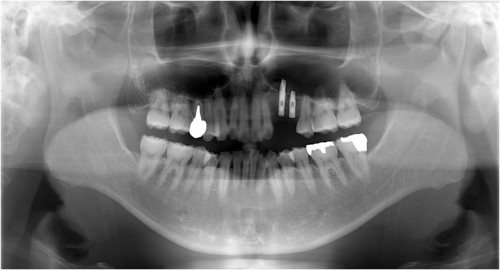

術 前

同拡大写真(根が破折しました)

抜歯後→インプラント埋入前

インプラント埋入後→被せ物装着

同パノラマ写真